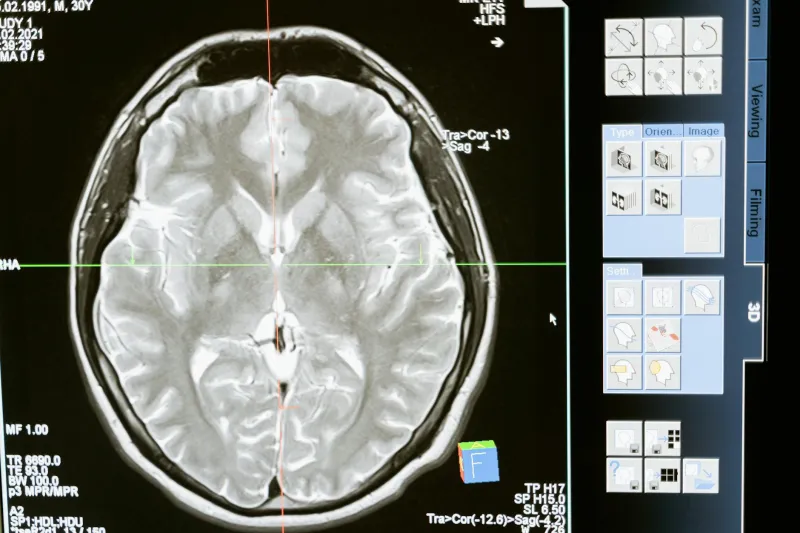

Modern neuroscience has tools Sperry could never have imagined. fMRI scanners can watch healthy brains in action, revealing how different regions activate during various tasks. The results consistently contradict the left-brain/right-brain personality model.

When people solve math problems — supposedly a "left-brain" activity — both hemispheres light up with activity. Creative tasks like improvising music or writing poetry engage networks spanning the entire brain. Even basic functions like recognizing faces or understanding language require coordination between hemispheres.

A 2013 study from the University of Utah analyzed brain scans from over 1,000 people, specifically looking for evidence of "left-brained" or "right-brained" thinking patterns. They found none. While individuals showed preferences for certain neural networks, these patterns didn't align with hemisphere-based personality categories.